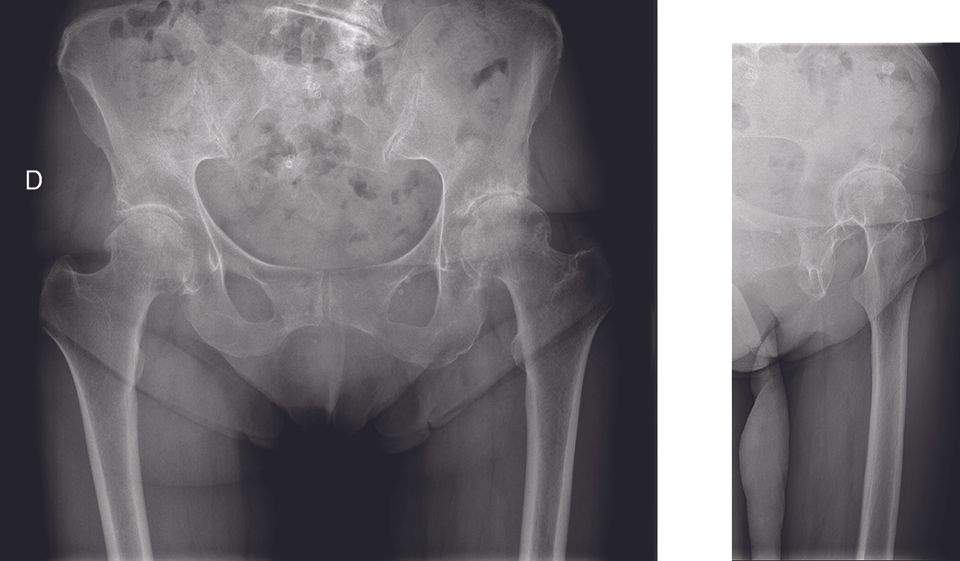

Webinaire Ruptures de l'anneau pelvien : quelle prise en charge de l'urgence au traitement définitif ? , Pierre Martz CHU François Mitterrand, Dijon, France , Sébastien Lustig Hôpital de la Croix-Rousse, Centre Albert Trillat, Lyon, France , Axel Gamulin Hôpitaux Universitaires de Genève, 4 rue Gabrielle-Perret-Gentil, CH-1211 Genève, Suisse , Medhi Boudissa Clinique universitaire d’orthopédie et de traumatologie du sport - Hôpital Michallon - Alpes Trauma Centre, Grenoble, France mars 2021